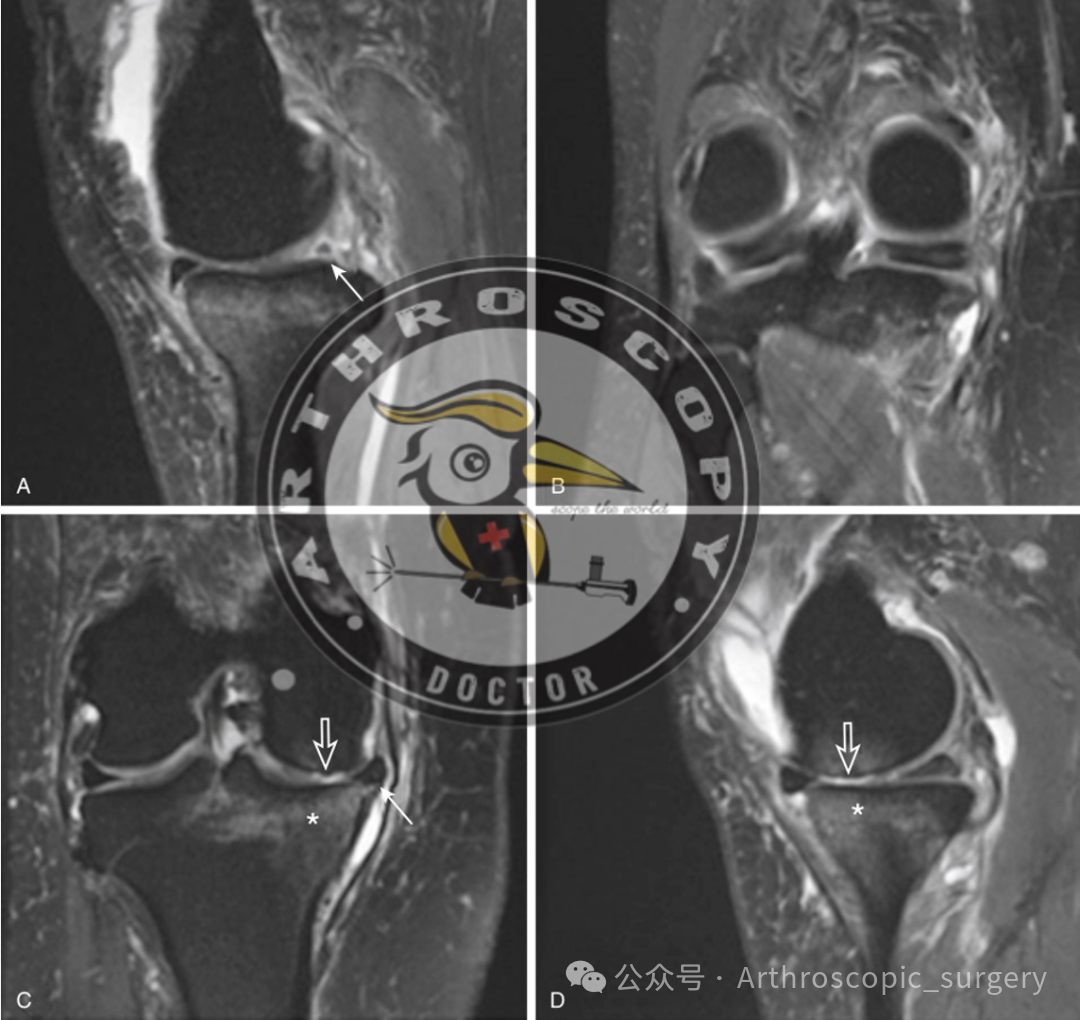

内侧半月板外突是MRI诊断MMRTs可靠且有用的征象。

推荐意见 17:

“鬼影征(Ghost sign)”是MRI诊断MMRTs可靠且有用的征象。

推荐意见 18:

“截断征”(多见于冠状位MRI)是MRI诊断MMRTs可靠且有用的征象。

推荐意见 19:

内侧半月板根部附着处(胫骨平台后内侧)的骨髓水肿,可作为MRI诊断MMRTs的参考征象。